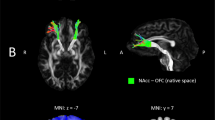

In comparison to HC, individuals with AN showed lower rsFC between the NAcc and the insula encompassing the adjacent temporal gyrus and operculum (pFWE < 0.001) and the supplementary motor area (pFWE < 0.001) (Fig. 1; Table 2).

Figures (a, b) display lower functional connectivity between the nucleus accumbens and (a) the right insula (NAcc-insula; pFWE < 0.001); (b) the left supplementary motor area (NAcc-SMA; pFWE < 0.001) in the AN group compared to HC. Color bar represents t-values. Results are corrected and displayed at family-wise error (FWE) probability pFWE < 0.05 threshold, cluster-extent. AN anorexia nervosa, HC healthy controls.